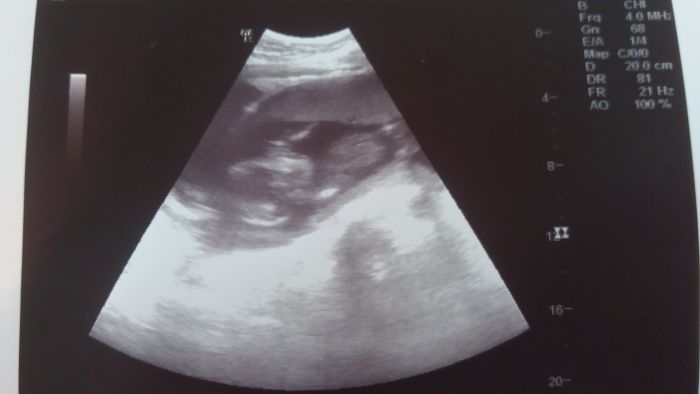

Stejně,kdyby mi neřekl že je toto pohlaví holčičky asi bych to nepoznala

. Fotku celé mrňavky mi dr.neudělal. Jen toto. Příště (za měsíc) budu na něj tlačit , ať jí hezky zabere.